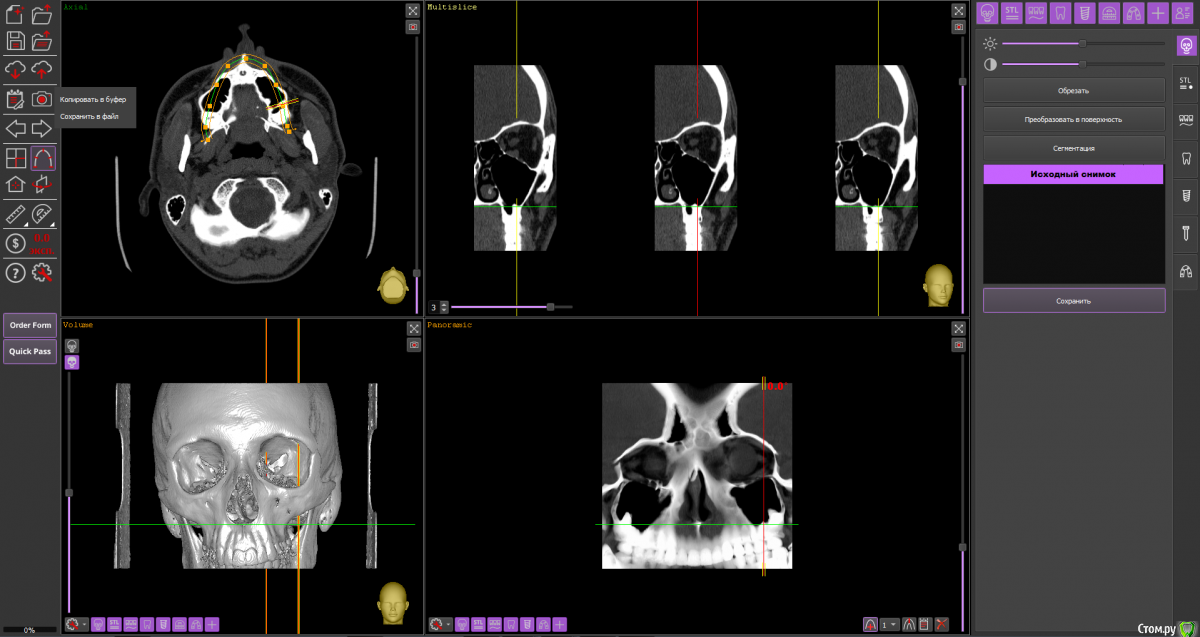

Dmitriytd Опубликовано 19 августа, 2020 Поделиться Опубликовано 19 августа, 2020 Здравствуйте, пожалуйста, посмотрите КТ( сделано в стоматологической клинике). Беспокоят проблемы с носом(постоянные прозрачные выделения, боли в пазухах, особенно при наклоне головы вниз). Знакомый лор посоветовал проверить на одонтогенный гайморит и я вспомнил, что делал КТ два года назад.Ссылка на КТ:https://yadi.sk/d/64pLNRildrWt5A Ссылка на комментарий

Dmitriytd Опубликовано 11 сентября, 2020 Автор Поделиться Опубликовано 11 сентября, 2020 Два года -кт не актуаленЗдравствуйте, сделал новое КТ. Пожалуйста, посмотрите:https://yadi.sk/d/1sbzO9z0QrurZg Ссылка на комментарий